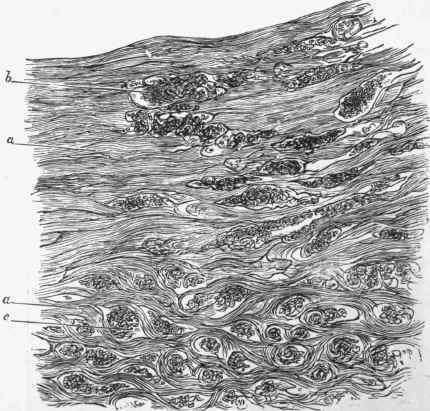

Fig. 456. - Section of cancer of uterus under a very low power, showing mode of advance into wall of uterus, a, muscular substance of uterus, interrupted frequently (as at 6) by masses of cancerous structure. At lower part of figure (at c) the muscular substance is still more frequently interrupted and the tissue has quite an alveolar appearance, the muscle partly forming the stroma, x 22.

Infiltrating cancer begins as an infiltration of a limited part of the portio vaginalis, and extends more or less round the external os. By and by the whole portio vaginalis is converted into a hard, irregularly prominent tumour. At first the infiltration is confined to the mucous membrane and submucous tissue, but by degrees it spreads both deeply and laterally. It insinuates itself into the muscular substance of the uterus, separating and breaking up the muscular trabecule, which come to form a kind of rough stroma for it (see Fig. 456). It also passes into the vagina, infiltrating its wall. Very soon ulceration of the surface sets in, and in its subsequent course there is a progressive ulceration and infiltration, the former following the latter. The infiltration passes into the body of the uterus, but does not usually reach the fundus before the death of the patient. If the parts be examined post mortem (Fig. 457), it will be seen that an irregularly excavated ulcer occupies the adjacent parts of the uterus and vagina, rendering their respective limits inappreciable. Then, outside this, there is the whitish cancerous tissue, which extends into the uterine substance some lines beyond the ulcer.

The microscopic examination of this form of cancer shows masses of epithelial cells, usually of considerable size, arranged irregularly in the alveoli, the stroma being largely formed by the remains of the struc tures into which it has infiltrated.